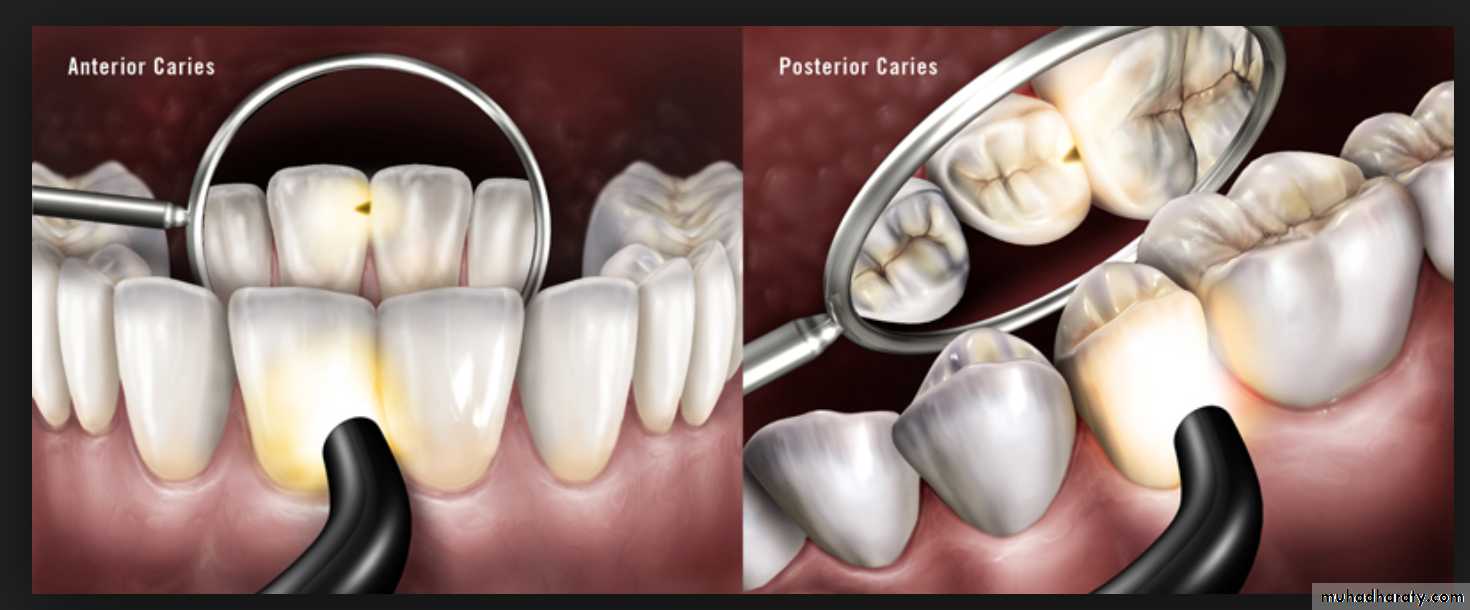

Visual examination

Use of visual examination only, is known as the European method, while use of sharp or blunt probe in visual tactile system is popularly known as the American system for diagnosis of dental caries.Visual examination for diagnosing dental caries is a very popular method. It is based on the criteria such as:

Cavitation, surface roughness, opacification and discoloration of clean and dried teeth under adequate light source.

Cavitated Lesions

Where there is visual breakdown of a tooth surface, it is classified as cavitated carious lesion. An active cavity on a smooth surface has soft walls or floors as shown below:Secondary caries